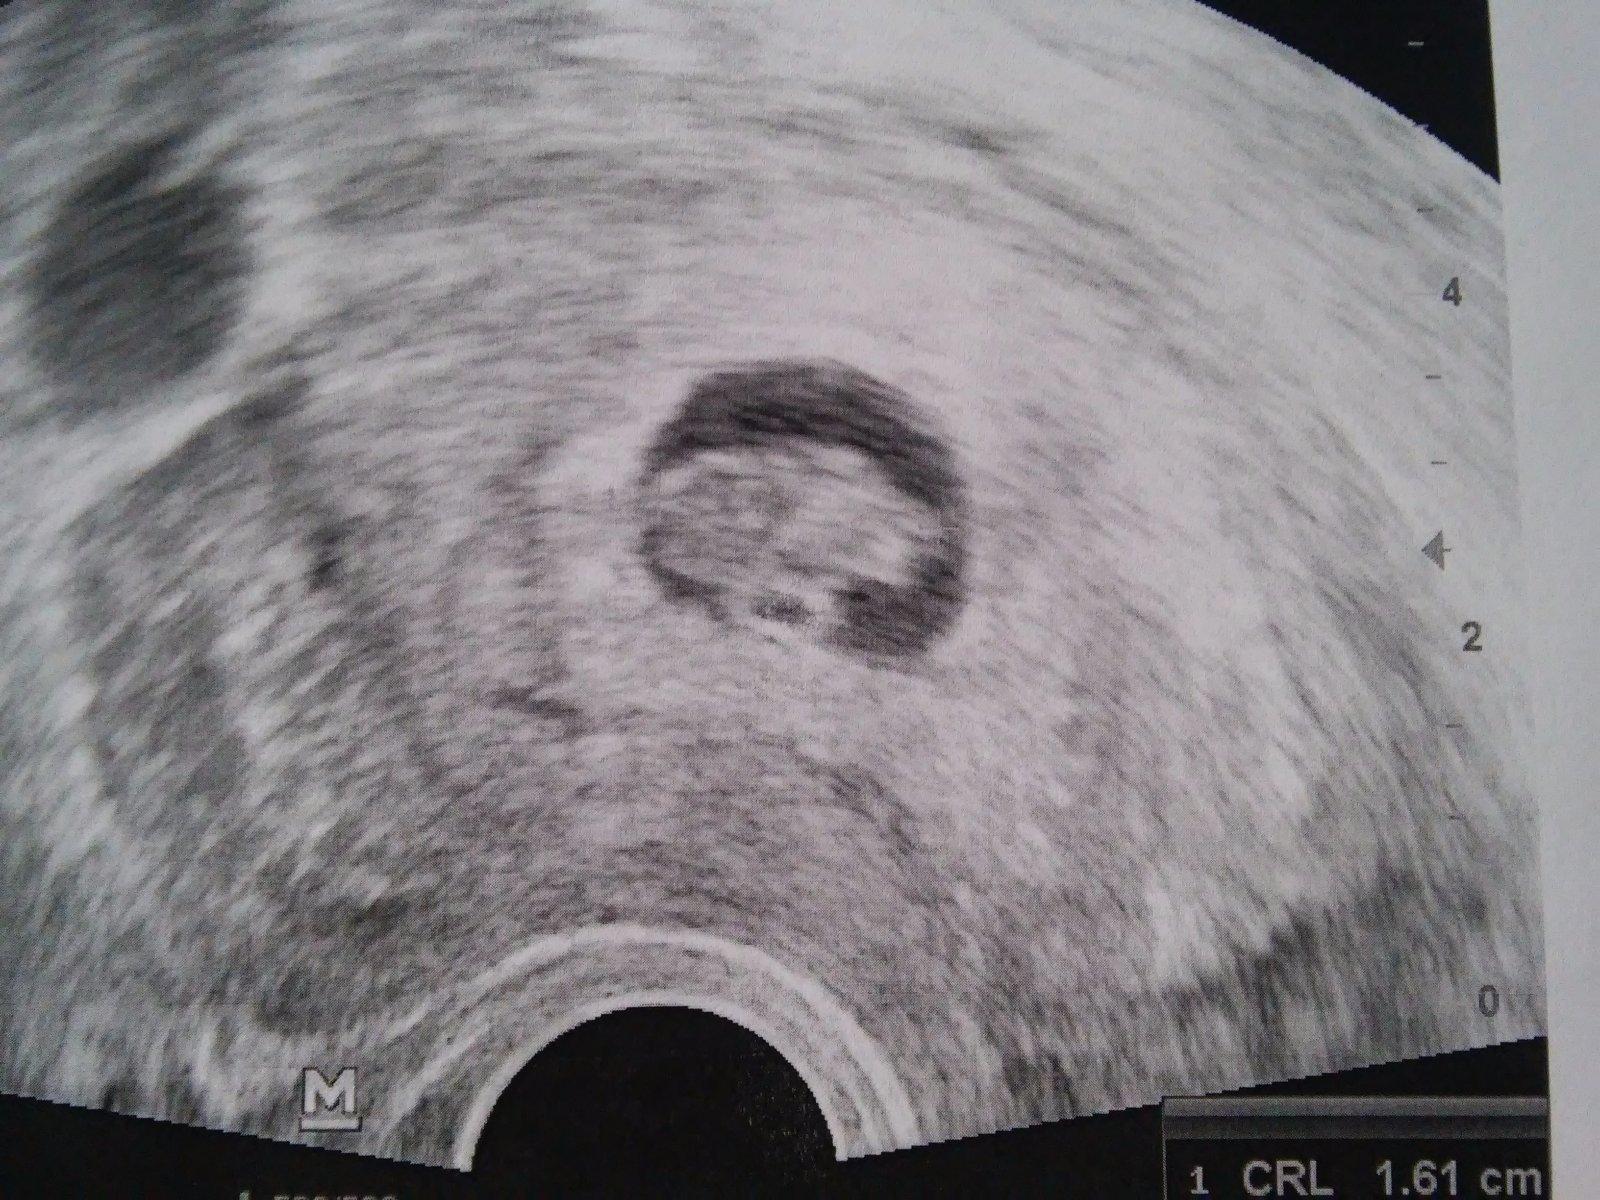

To je hezky ty briska ❤ ja se na nej hrozne tesim 😇 tady je moje v 12tt